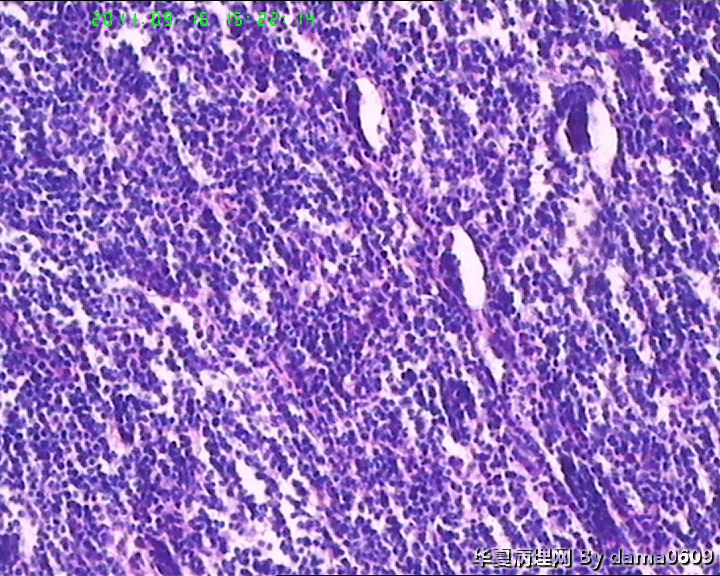

• 背部肿物,急请老师看看!!图3

图3